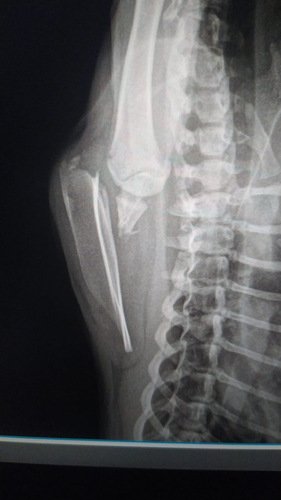

Infelizmente, recentemente, João enfrentou um terrível acidente. Ele escorregou e caiu de uma altura assustadora de 15 metros, resultando em uma fratura na escápula.

De momento tivemos um gasto de R$ 1.600,00 contando com as diarias que ele esta internado, estamos a procura de um ortopedista mais em conta, porem tivemos um orçamento medio de alguns ortopedista em Guarulhos de 3 mil a 6 mil reais, sem contar fisioterapia dele.